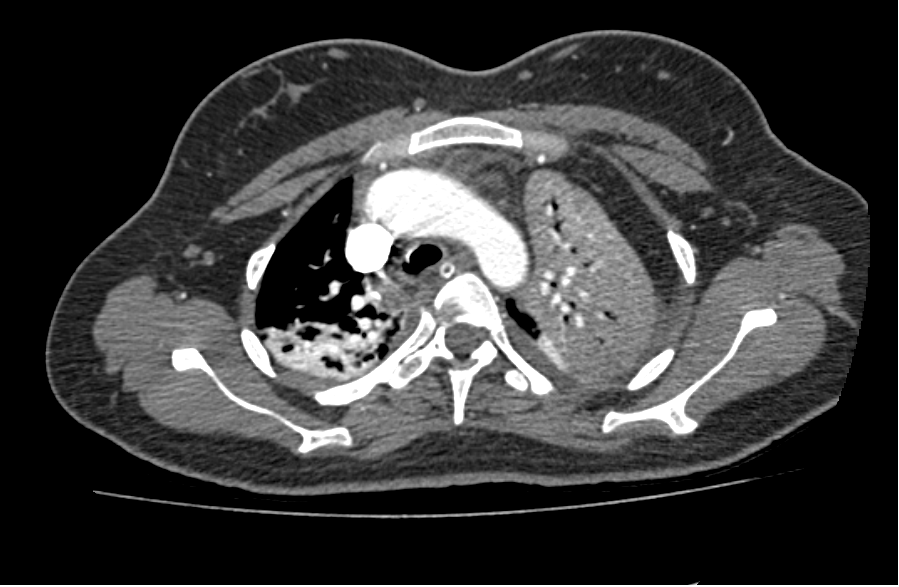

Figure 2. Contrast enhances the computed tomography scan of the chest. Transverse sections show abdominal contents in the left hemithorax with a collapsed ipsilateral lung. Moderate right-sided pleural effusion was also noted. Note is made of nasogastric tube in the stomach, seen in the left hemithorax. The stomach, descending colon, and omentum can be seen here in the left hemithorax compressing the ipsilateral lung.

A 27-year-old woman presented to the emergency department with complaints of shortness of breath and cough with sputum for the last three days that had worsened since the morning of presentation. Her history was significant for gestational amenhorrea of 32 weeks. This was her second pregnancy. Her vital signs were within the normal limits. A physical exam revealed absent breath sounds on the left side and a gravid uterus of about 30 weeks. A chest x-ray was done which showed air fluid levels in the left chest with upward pointing meniscus. The authors’ differential included a diaphragmatic hernia, diaphragmatic eventration, hydatid cyst, and loculated empyema. An obstetrician was consulted, and after an examination, they declared that the patient was in labor. She delivered a healthy baby through normal vaginal delivery. After labor, she was comfortably lying in bed with normal vital signs and no active complaints. However, a little later, the patient started to become tachypneic and tachycardiac. Her respiratory rate was more than 50 per minute and heart rate was more than 140 per minute. An electrocardiogram was done which showed sinus tachycardia. She was shifted to the intensive care unit and was intubated for progressing respiratory failure. A nasogastric tube was passed and approximately more than two liters of gastric content was aspirated. An urgent echocardiogram was obtained which showed a right ventricle strain and a dilated Inferior vena cava without respiratory variation. The patient was urgently shifted for a computed tomography of the chest with intravenous contrast, which revealed a large diaphragmatic hernia on the left side. The stomach, omentum, splenic flexure of the colon, the descending colon, small bowel, spleen, and tail of the pancreas were all present in the left chest cavity. There was a mediastinal shift to the right, and the left lung was collapsed. The right lower lobe also showed signs of compression atelectasis.